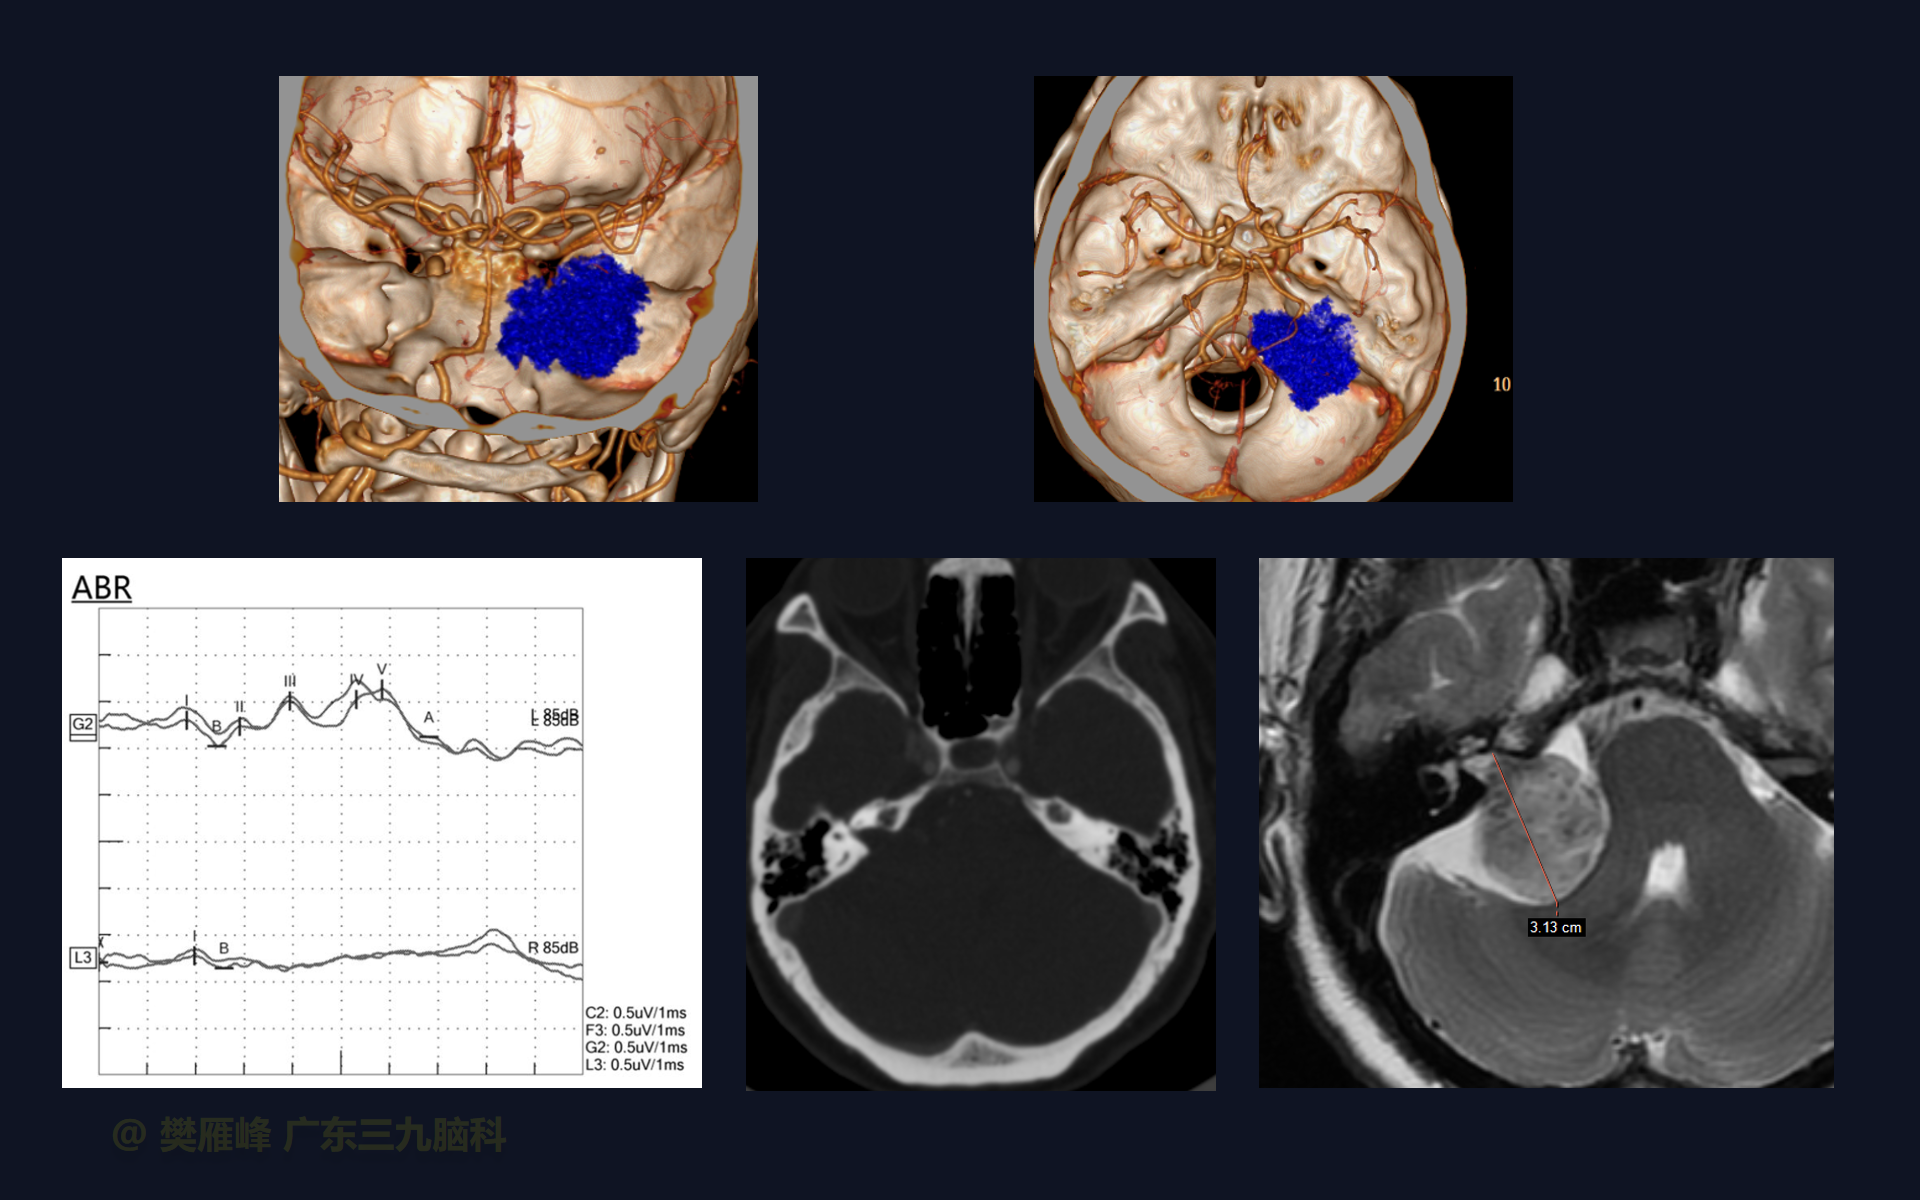

VS的大小和体积都与听力水平呈正相关,手术切除VSs后保留听力的最可靠的预测因素是肿瘤的大小、术前听力水平和BAEP的质量。

在这个二维手术视频中,展示了一种经枕下乙状窦后入路肿瘤包膜下分离并保留面神经。患者是一名53岁的男性,有1月的左耳听力下降、无步态不平衡病史,神经影像学显示右侧桥小脑角区T1低信号,T2不均匀高信号,DWI序列呈等、低信号,增强不均匀强化的听神经瘤。他接受了经乙状窦后入路保留面神经的方法,以实现肿瘤全切除。术后轻微面瘫,听力同术前改变,神经影像学显示肿瘤全部切除。我们展示了包膜下切除肿瘤和保护面神经的细微差别和技术要点。

在这段手术视频中,展示了一名53岁男性的病例,他因右耳听力下降1月余发现的右侧听神经瘤